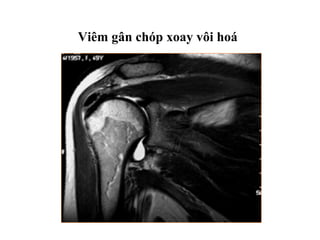

Viêm gân chóp xoay vôi hoá

Viêm gân chópxoay vôi hoá